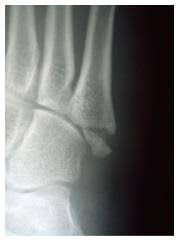

Surgery on fractures is very much dependent on what bone is broken, where it is broken, and whether the orthopedic surgeon believes that the break is at risk for moving out of place once the bone fragments have been aligned.

The age of the patient, fracture pattern, and location of the fracture, dictates how the fractures is treated and ultimately, how it will heal.

Treatment may involve surgery, and recovery can take up to four months. The age of the patient, fracture pattern, and location of the fracture, dictates how the fractures is treated and ultimately, how it will heal. 6 steps for healing broken bone (fractures) faster. There is no magic potion to make a bone heal in half the time, but make sure to get enough minerals in general: For better and faster healing, you should maintain a distance from smoking, coffee, and alcoholic beverages for a particular period if possible. Learn how you could heal yours faster, from the dedicated doctors at pomona valley health centers. Fractures need to be immobilized in order for them to heal. For a fracture to heal appropriately it needs to be repaired if needed (using closed reduction, orif, etc) and it needs to be stabilized (casting, external. How long does it take to heal a broken bone? A jones fracture is a type of fracture in your foot. The current drug for diabetic patients with. A jones fracture is a fracture of the bone on the pinky toe side of your foot, the fifth metatarsal bone. So how do i help a my broken bone heal faster?